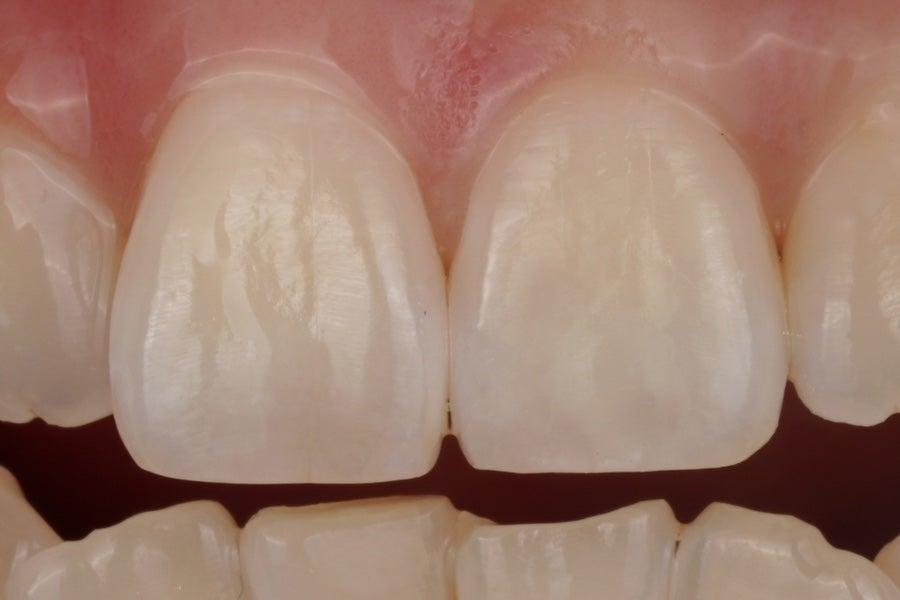

확대 사진

레진으로 앞니를 제대로 치료하려면

Layering Technique이 필요하다고

이 포스팅을 통해 알려드렸죠?

다양한 색상의 레진을

적재적소에 한겹한겹 쌓듯이 칠해야합니다.

그래서 치아 색상이 부위별로

자연스러운 그라데이션을 보이도록 해야해요.

이분도 역시

반점이 있던 부위가 다른 부위와 티나지않고

자연스럽게 보이도록

그라데이션을 주었습니다.

씹는 면으로 갈 수록

색상은 사라지고 어두워지다가

끝에 가서는 다시 하얗게 밝아지는

자연치아의 특징을 재현해드렸어요.

즉, 치과 전문용어로 말씀드리자면

투명층과 Halo(헤일로 이펙트)를 재현해드렸습니다.